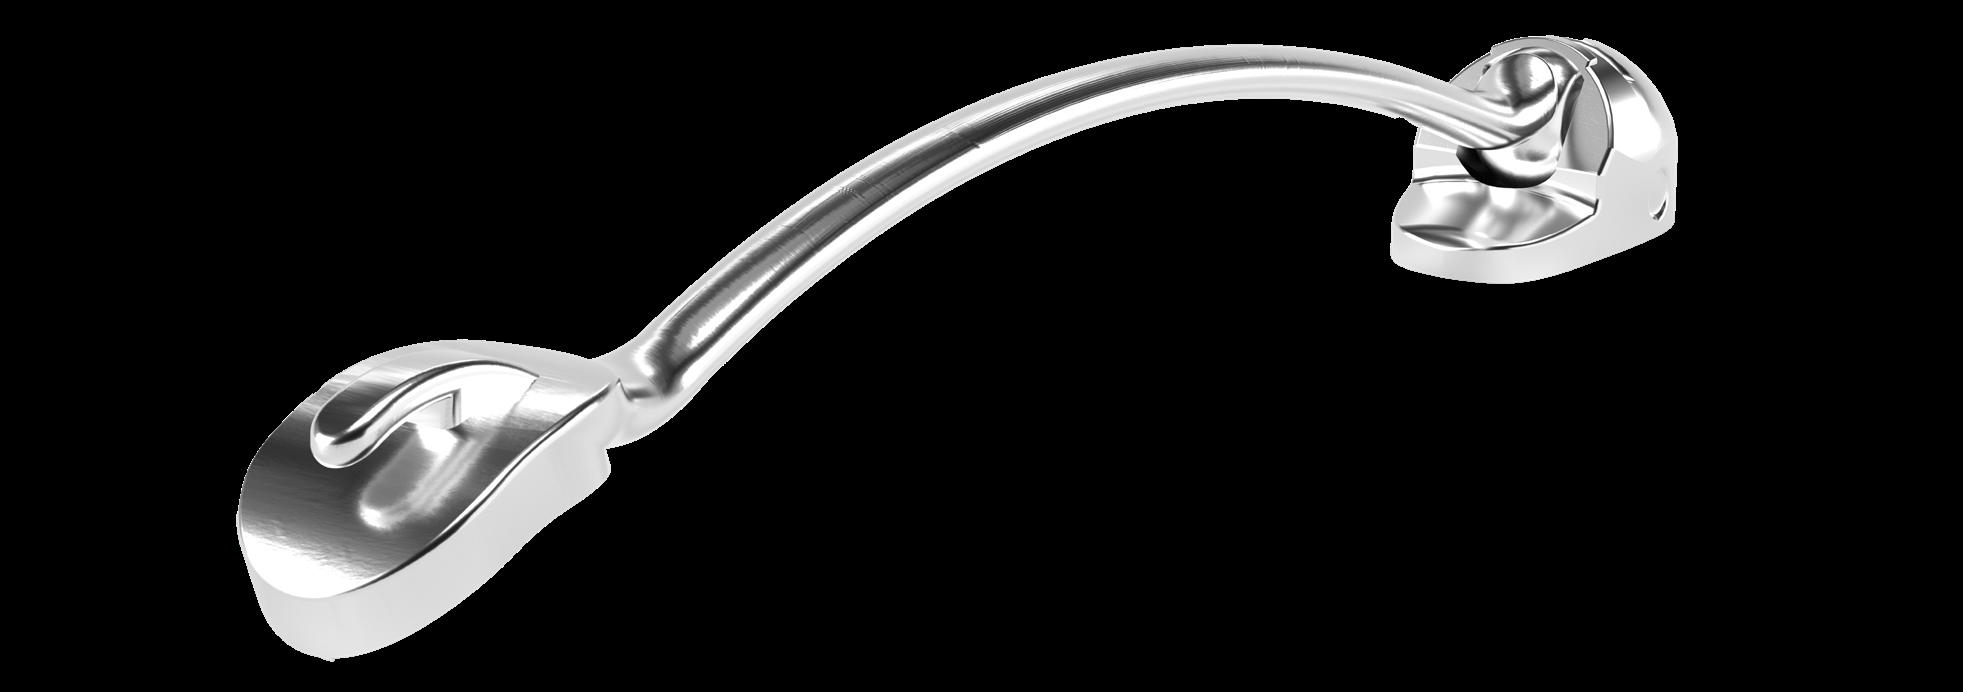

Carriere Motion 3D Appliance

Fastrack your orthodontic treatments. Save 6 months or more.

The SAGITTAL FIRST™ Philosophy is a time-tested approach that standardises, simplifies, and shortens Class II and Class III treatment times. It employs the Carriere Motion 3D Appliance to treat the AP dimension at the beginning of treatment before placing brackets or aligners. By resolving the most difficult part of treatment first, you can achieve a Class I platform in 3 to 6 months, shortening total treatment time by a minimum of 6 months1. You know how excited patients and parents become when you mention shorter treatment times.